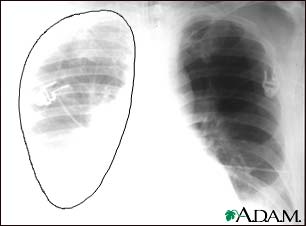

A chest x-ray is an x-ray of the chest, lungs, heart, large arteries, ribs, and diaphragm.

Images